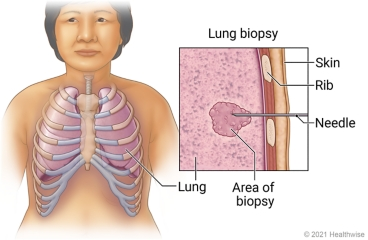

Lung biopsy (લંગ બાયોપ્સી):

- લંગ બાયોપ્સીમાં લંગ્સમાંથી લંગ ટીસ્યુનું સેમ્પલ કલેક્ટ કરવામાં આવે છે અને તેનું એક્ઝામિનેશન કરવામાં આવે છે. જેથી લંગ કેન્સર, લંગ ઇન્ફેક્શન અને ડીઝીસને આઇડેન્ટીફાય કરી શકાય છે.

લંગ બાયોપ્સી કલેક્ટ કરવા માટે જુદી જુદી મેથડ નો ઉપયોગ કરવામાં આવે છે:

- બ્રોન્કોસ્કોપિક બાયોપ્સી (Bronchoscopic biopsy)

- ઓપન લંગ બાયોપ્સી (Open lung biopsy)

- મેડિયાસ્ટીનોસ્કોપી (Mediastinoscopy)

- નીડલ બાયોપ્સી (Needle biopsy)